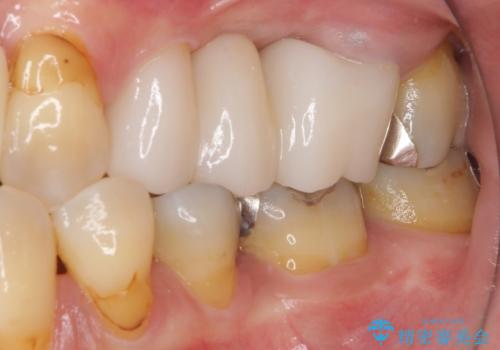

ものが挟まる原因は、保存困難なほど歯肉から露出していた歯根にあったため、抜根することで気になっていた問題は解消されました。

外観も審美的になり、患者様には大変満足していただきました。